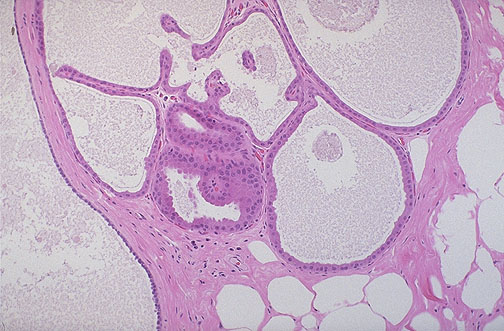

At low power, the prominent cysts of fibrocystic changes are shown. The cysts are lined by a single epithelial layer of varying height.